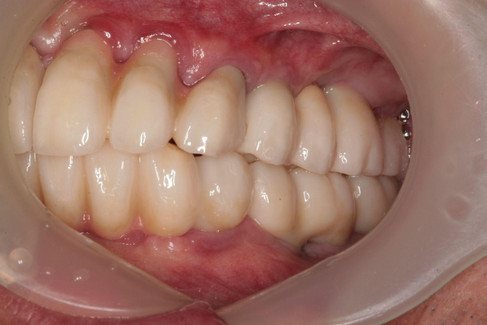

5️⃣ Final Restoration

The final prosthetic restoration was delivered 8 months after surgery.

[7-Year Follow-Up]

The 7-year follow-up periapical radiograph shows no significant bone loss, indicating long-term success and a favorable prognosis.